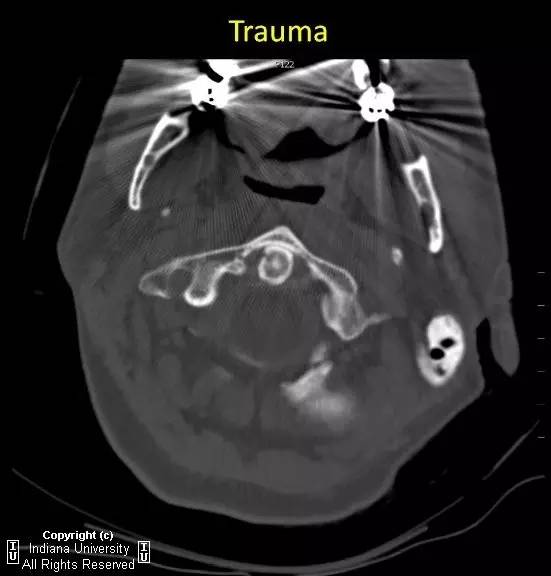

【病例】II型齿状突骨折1例

【影像学表现】

急性横行齿突骨折,C2椎体与齿突尖分离约7mm。齿突尖仍与C1前弓正常排列。

【诊断】II型齿突骨折

Type 2 odontoidprocess fracture